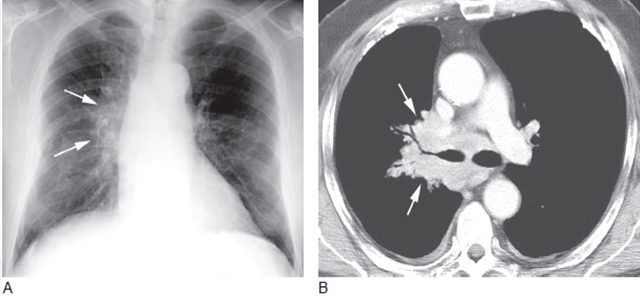

五、肺门肿块或淋巴结增大

影像学上肺门增大提示起源于中央区域的原发性肿瘤(模糊肺门肿块)(图17) 或周围型肺癌肺门淋巴结转移(边界清楚肺门肿块)(图18)。鳞癌常见。肺门淋巴结增大与中央肿块融合是小细胞肺癌的特征(图13)。

图17 石棉暴露后的右肺门肿瘤

A. 胸片显示边界不清的右肺门肿块(箭头),为典型的起源于肺门的肿瘤,可见石棉暴露后引起的胸膜增厚和钙化; B. 大的、边界不清的右肺门肿块包绕致右肺上叶支气管狭窄,为典型的小细胞肺癌的征象

图18 周围型肺癌转移伴左肺门淋巴结增大(箭头)

肺门肿块边缘锐利